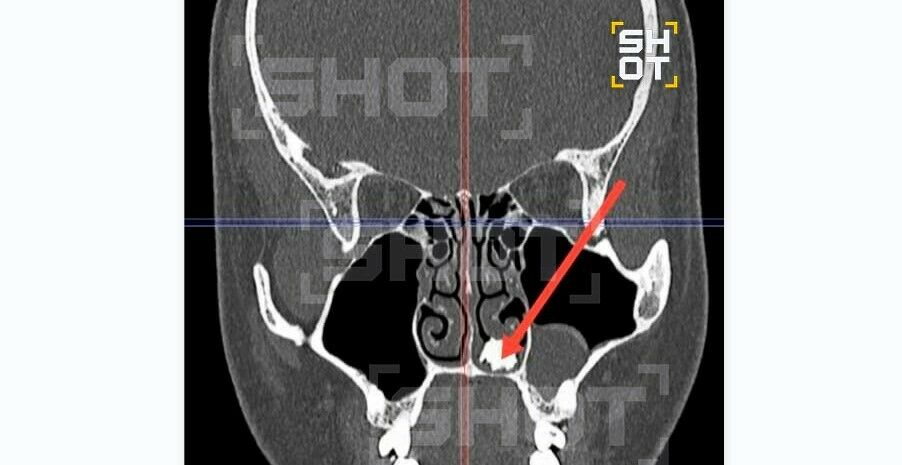

Медики, осмотрев пациента, отправили его делать рентген. Снимок показал, что в носу молодого человека есть посторонний предмет – оказалось, что это молочный зуб.

Врачи извлекли зуб из носа и уже через несколько дней выписали пациента. Как зуб оказался в неположенном месте, неясно. Информацией и фото делится Telegram-канал SHOT.